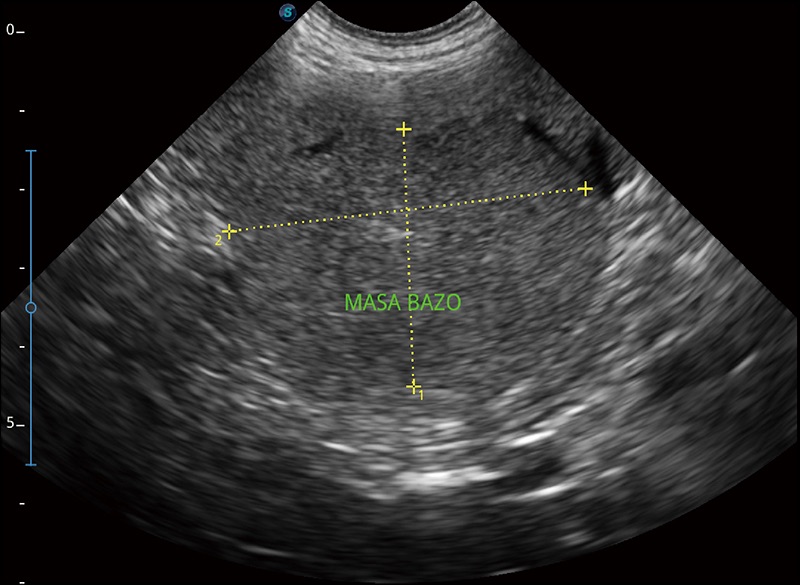

α1卓越的图像质量和便捷的工作流程,使每位宠物医生都能轻松扫查。其全面的兽用应用功能和紧凑型的结构设计,可以满足动物检查的多种需要。专业的预设检查模式和多领域测量软件包有助于为不同类型的动物提供检查, 让宠物医生能够出色的完成工作。

可实时观察感兴趣区域和病变位置